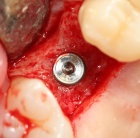

Lernen Sie mit eindrucksvollen Full Hd Videos das operative Vorgehen wie bei einer Live OP, ohne die üblichen Wartezeiten.

Werden Sie fit für Ihren ersten eigenen Sinuslift.

Gewinnen Sie Einblicke, die Ihnen sonst verwehrt bleiben. Bekommen Sie Hintergrund Wissen, das es Ihnen möglich macht, die Qualitätskriterien Ihres Implantat Systems wirklich zu beurteilen.

Erfahren Sie, welche Fehler Sie unbewusst beim Implantieren machen können. Lernen Sie Ihr eigenes Implantat System anhand des Bohrprotokolls einschätzen und zu beurteilen. Wichtige knochenbiologische Kenntnisse.

Eignen Sie sich wissenschaftlich aktuelles Wissen an und vermeiden Misserfolge, die sich bisher nicht erklären konnten. Warum verkürzt eine perfekte Primärstabilität die Einheilzeit.